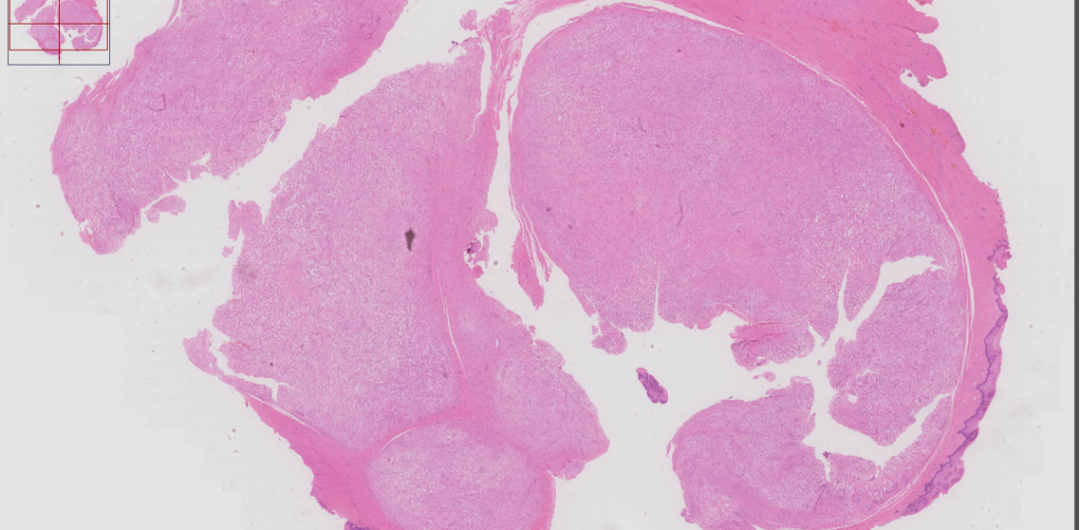

阴道前壁包块)灰红结节状组织一块,大小2.8*2.5*1.0cm,组织切面灰红灰白质中,部分半透明,界限清。

肿瘤位于粘膜下,呈多结节状生长,界限尚清。